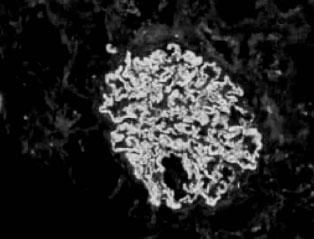

光镜下肾小球基本正常,免疫荧光检查一般无免疫沉积物,电镜下的弥漫性上皮足突消失或融合为其典型病变(图2—5)。有时也可见到局灶的系膜区有电子致密物。在微小病变性肾病病程发展到后期出现的局灶硬化性损害。微小病变性肾病有时在免疫荧光下也可见系膜区有IgM、IgA或C3沉积,一般很轻微。系膜细胞增殖和IgM沉积如同时出现,常提示对激素疗效差或对激素的反应延迟,并且使疾病进展的可能性增大。

图2—5 微小病变性肾病,上皮细胞足突融合(电镜 x8000)